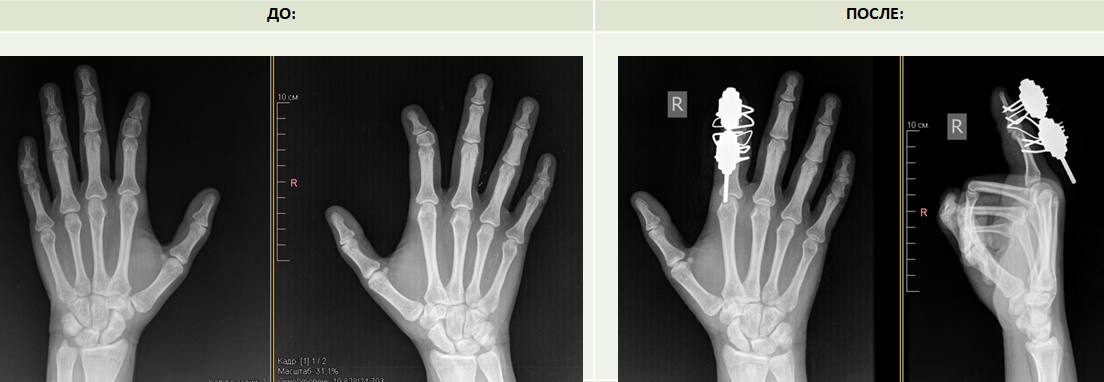

В НМИЦ травматологии и ортопедии имени Г.А. Илизарова обратились сёстры-близнецы с одинаковой патологией кисти. У них один и тот же вид врожденной деформации – клинобрахидактилия.

Патология характеризуется укорочением средних фаланг и угловой деформацией пальцев, у пациенток наблюдались аномальное строение второго и пятого пальцев. У одной из сестёр деформация больше выражена на правой руке, у второй — на левой. Врачи центра впервые столкнулись с почти с одинаковой патологией у двух близнецов.

«Это и косметический дефект и функциональный, потому что указательный палец участвует в основных функциях кисти. В операционной мы устранили деформацию, сделав корригирующую остеотомию, и установили аппарат Илизарова для дозированной дистракции, чтобы компенсировать укорочение фаланг», — рассказала Ирина Чиркова.

Для удлинения укороченных фаланг пальцев по методу Илизарова понадобится в среднем три недели. На период фиксации в аппарате пациенток выпишут на амбулаторное наблюдение.